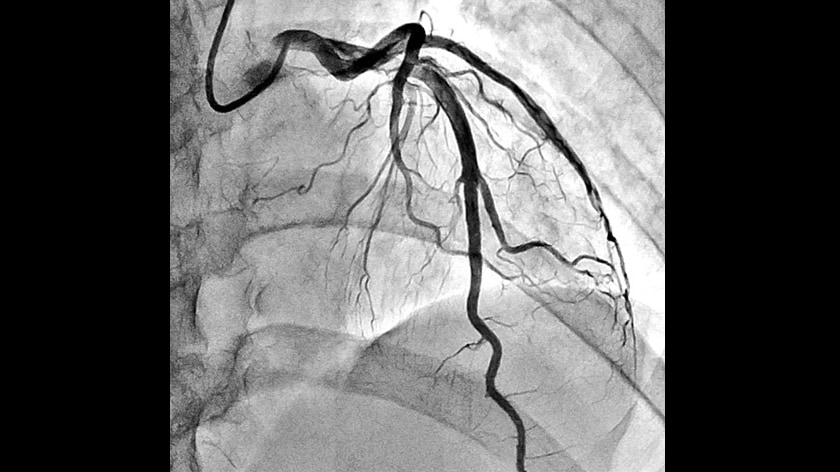

- Crossover Angiography System - Trinias series with SCORE Opera

Crossover Angiography SystemTrinias series

with SCORE Opera

The Trinias series with SCORE Opera is a Crossover Angiography System developed to provide solutions for the evolving challenges in medical treatment centers. This system is designed based on three core principles: ALARA (As Low As Reasonably Achievable) Design, Lean Design, and Sustainable Design.

IVR procedures are becoming increasingly complex and sophisticated, and require angiography systems that can achieve lower radiation doses, less contrast media use, and shorter examination times. Shimadzu's latest Trinias™ series angiography system comes with various features that support minimally invasive procedures ...